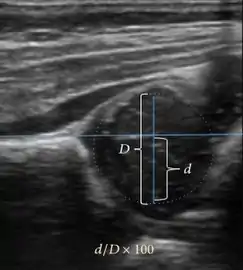

Ultrasound is the first-choice technique for diagnosis of newborns hip dysplasia. In experienced hands with appropriate technology, ultrasound can also be useful during the first year of life. Some European healthcare systems encourage universal ultrasound screening in neonates between the sixth and eighth weeks. Although it shows higher initial costs caused, it leads to significant reduction in the total number and overall costs of dysplastic hips undergoing operative and nonoperative treatment.[1]

Ultrasound allows categorizing pediatric hips, according to Graf’s criteria, in four main types: normal, immature, and dysplastic (subluxed and dislocated). This classification is based on measurements of the acetabular inclination angle (alpha), cartilage roof angle (beta), and infant age. The femoral head coverage can also be determined by dividing the length of the femoral head covered by the acetabular fossa and the diameter of the femoral head. Its lower normal limits are 47% for boys and 44% for girls (Figure 11).[1]

Figure 11:

Useful ultrasound measures in neonatal hip sonography, alpha and beta angles.[1]

Measurement of femoral head coverage.[1]